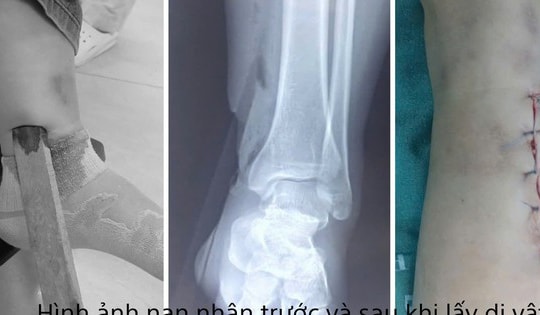

Tai nạn hi hữu: Đầu vít bắn xuyên vùng má thợ xây khi đang làm việc

22/09/2025 20:59

Trong lúc dùng súng bắn vít, một thợ xây làm văng đầu vít găm vào má phải một người gần đó. Dị vật kim loại cắm sâu, gây rạn xương gò má, nạn nhân đã được phẫu thuật khẩn cấp.